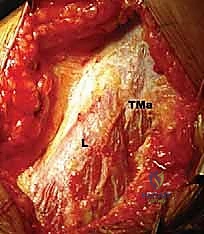

FIG 4 • B. The latissimus dorsi (L) is identified and separated from the teres major (TMa).

FIG 1 • A. Cadaveric dissection showing the interval between the teres major (TMa) and latissimus dorsi (L) tendons, with the radial nerve (R) deep to the latissimus and the axillary nerve (Ax) superior.